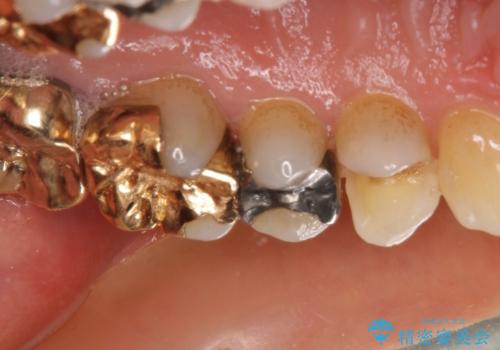

外れてしまった銀歯 セラミックインレーで自然な仕上がりに

- 奥歯の銀歯が外れてしまったため、セラミック治療を希望された患者様です。

セラミックインレーによる修復治療を実施しました。

正面から見える場所であったため、セラミックインレーで自然な口元にすることができました。